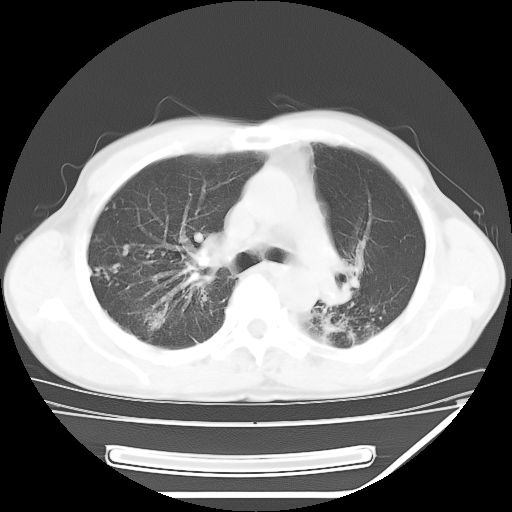

男,59岁,“结核性胸膜炎”30余年,胸部经常疼痛,多次x检查提示“肺部”炎症。腹部疼痛5日,b超提示:“肝内短管结石,余显示不清,建议进一步检查。”

两肺结核并右侧胸腔积液;脾脏、腹腔及腹膜后淋巴结结核[陈旧性];肝内胆管结石

两肺结核并右侧胸腔积液;脾脏、腹腔及腹膜后淋巴结结核[陈旧性];肝内胆管结石。直肠息肉?